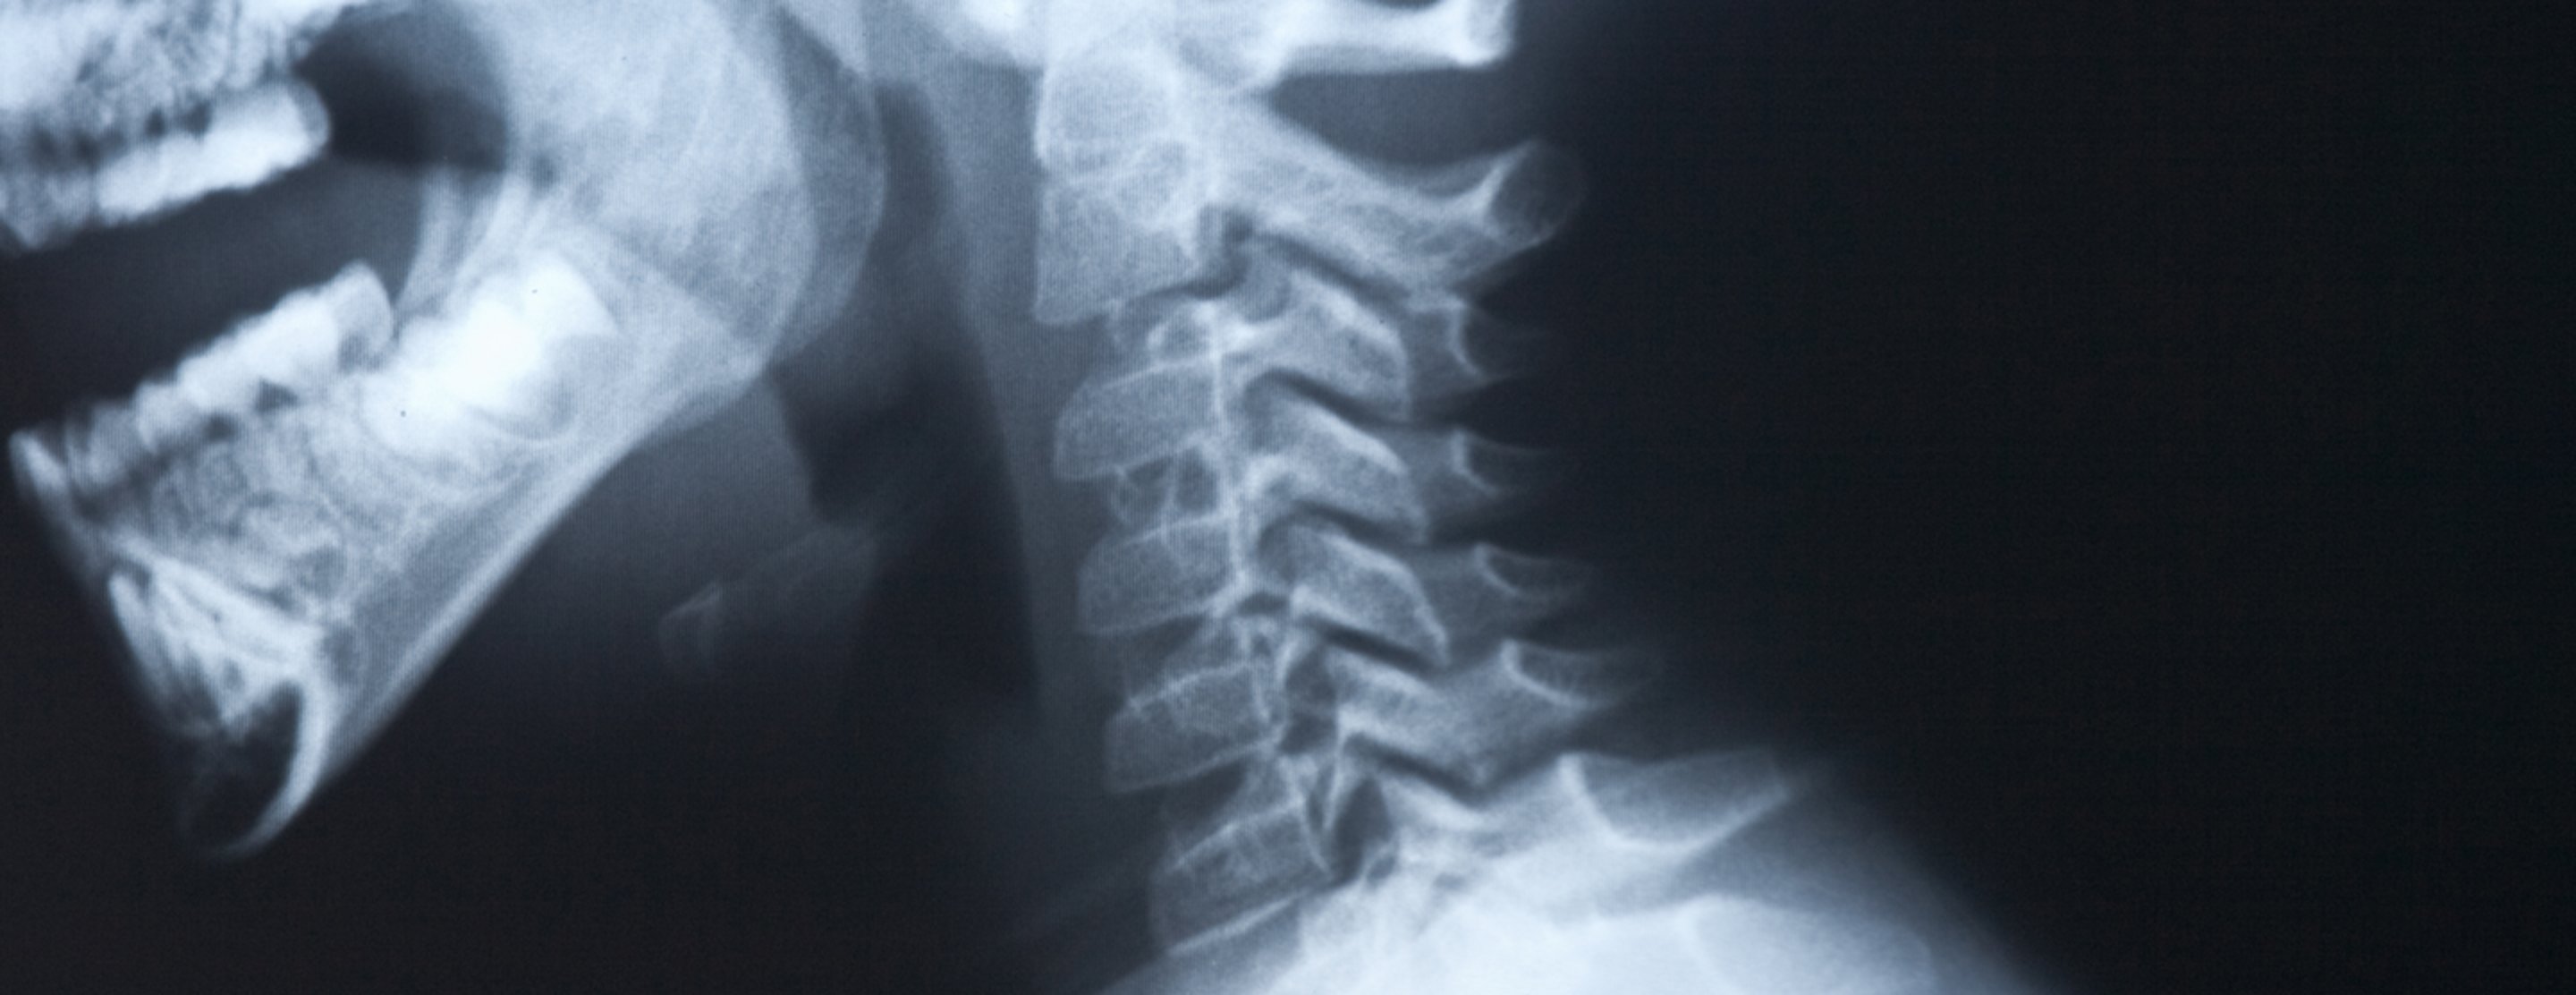

Измерение кифоза грудного отдела: Рентгеновские снимки